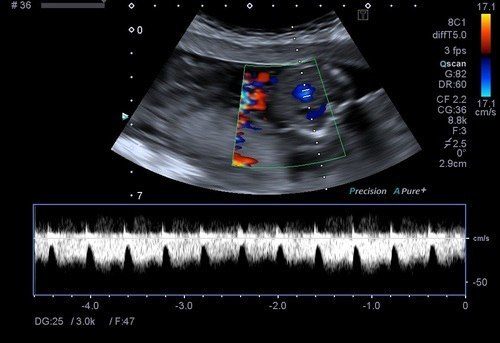

Obstetrik renkli doppler ultrason incelemesinde rahmi besleyen ana damarlar, plasentadan bebeğe doğru giden kordon damarları, bebeğin beyin ve karın bölgesindeki damarlar incelenir.